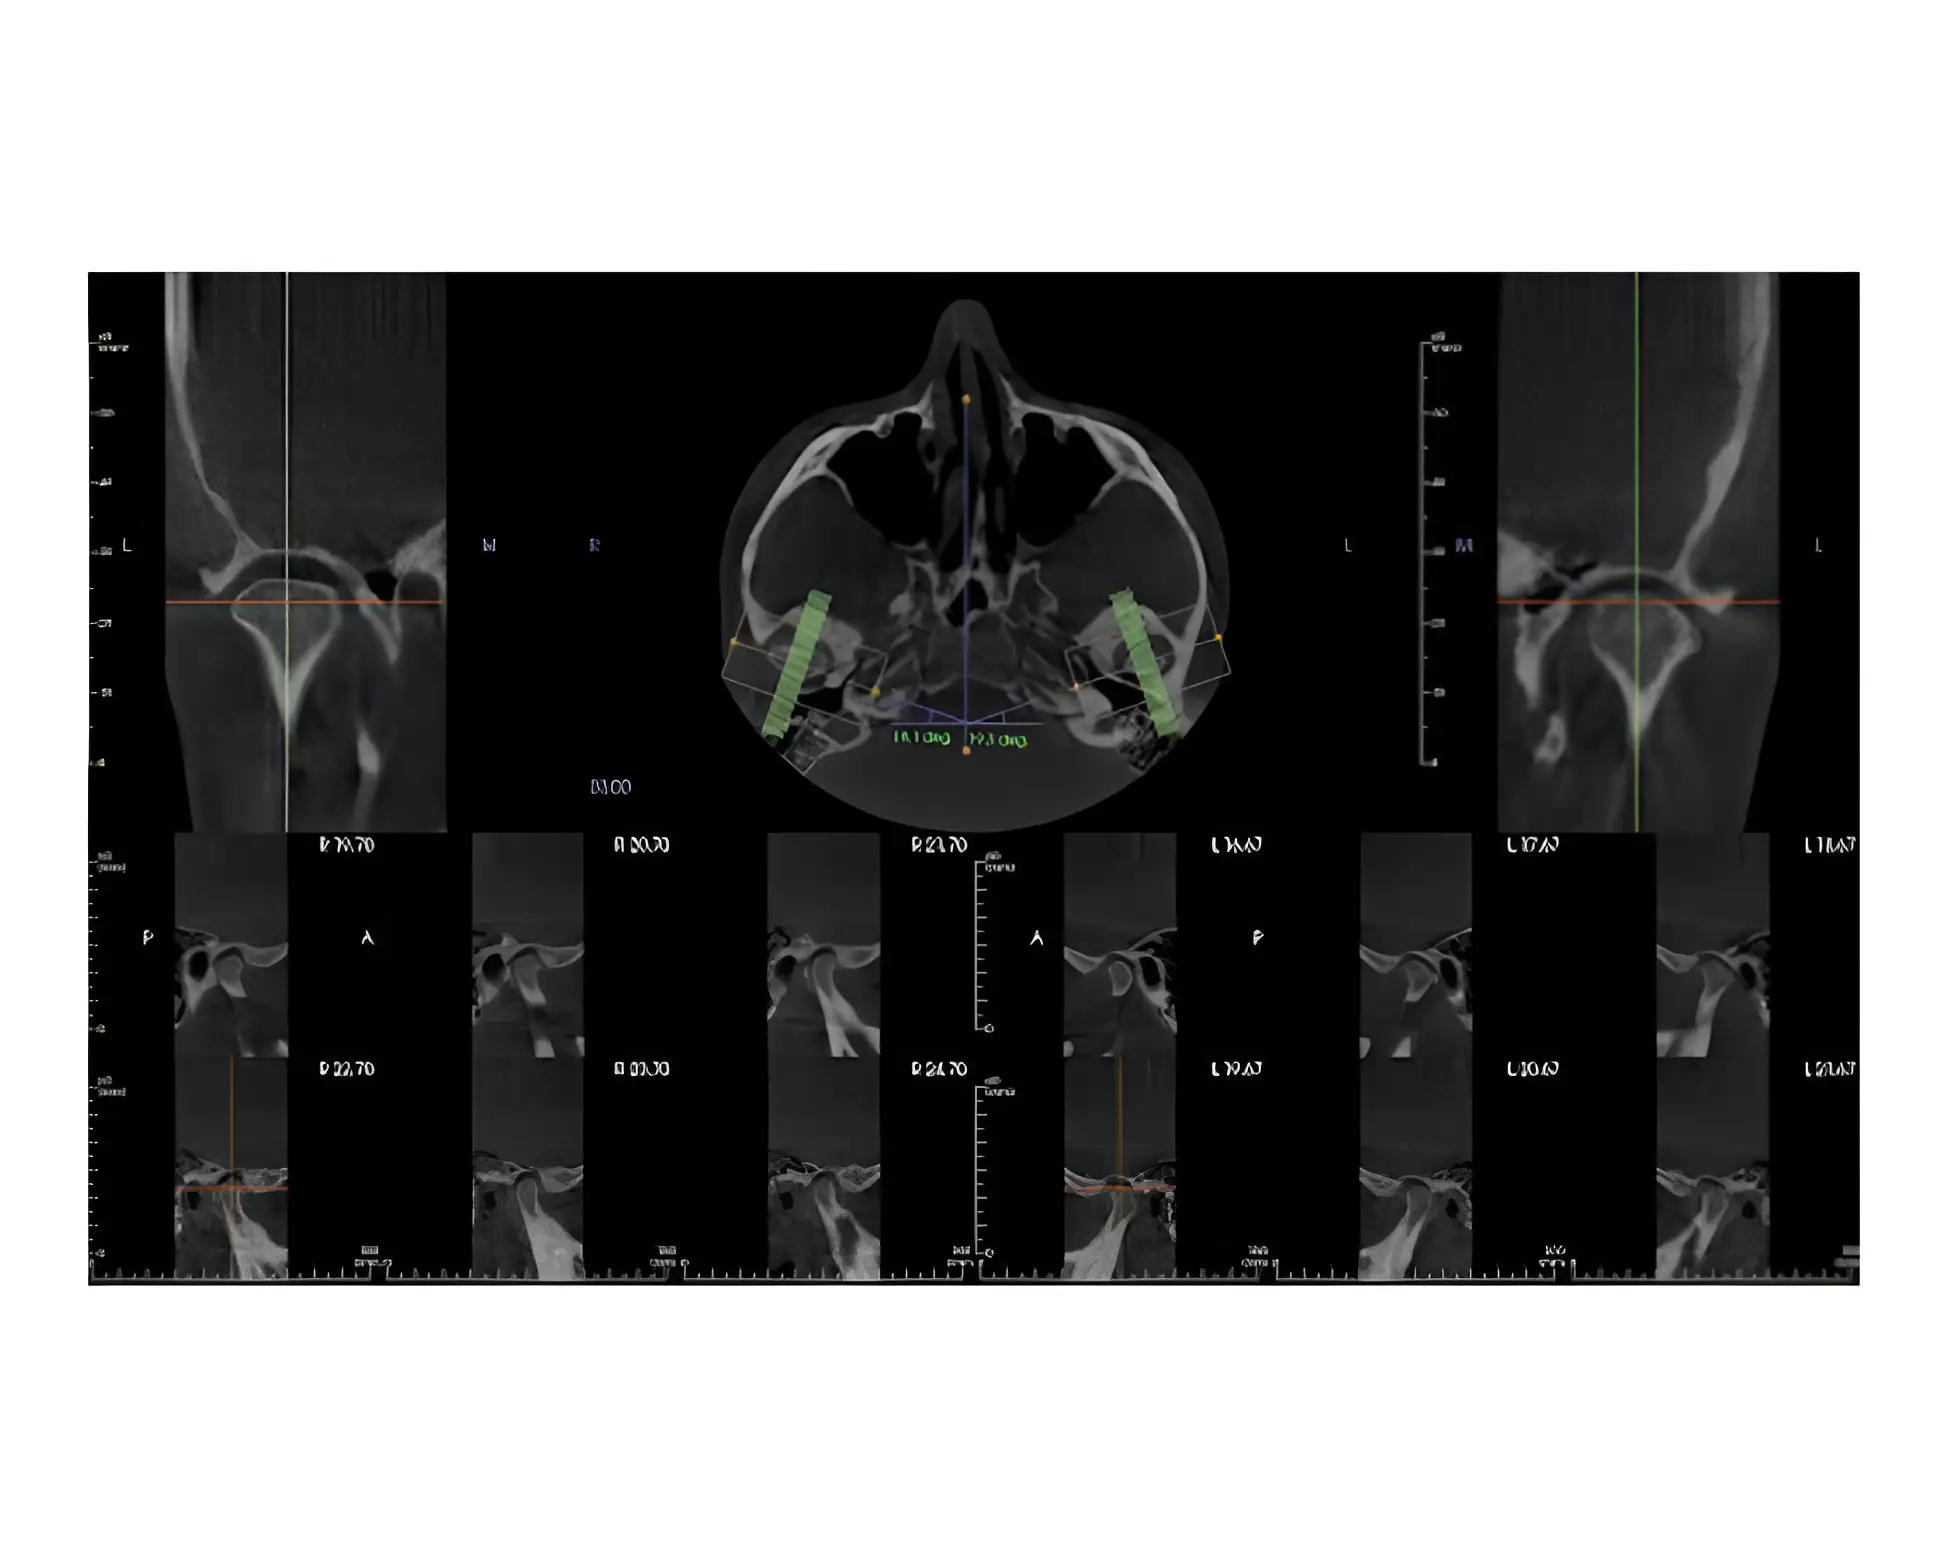

We will then bring you in for a series of diagnostic photos, a Trios intraoral digital impression, and 3D CBCT imaging of your teeth, your jaws, your airway, and your TMJ. Dr. Mindy and her staff will complete a clinical diagnostic workup, ask a few more questions, and have a conversation with you to gain a full picture of your needs.